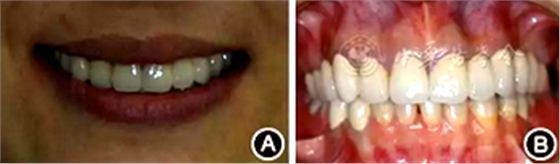

口腔衛(wèi)生狀況一般,菌斑指數(shù)0~2,鄰面少量軟垢;牙齦齦緣鮮紅、水腫、質(zhì)軟,出血指數(shù)2~3,余牙牙齦輕度水腫,出血指數(shù)0~2;全口探診深度2~3 mm,個別位點探診深度達4~5 mm,鄰面可探及附著喪失;未查及牙齒松動及根分叉病變;烤瓷固定橋修復(fù),冠邊緣密合度欠佳,位于齦下1~2 mm;、唇側(cè)崩瓷,邊緣暴露;上前牙牙齦線不協(xié)調(diào);缺失,右下后牙可摘局部義齒修復(fù),固定橋修復(fù);近中面銀汞充填,近中懸突及繼發(fā)齲;上前牙覆蓋下前牙牙冠的1/2~2/3(圖1)。

圖1 患者初診時臨床照片 A:正面微笑像;B:正面口內(nèi)像